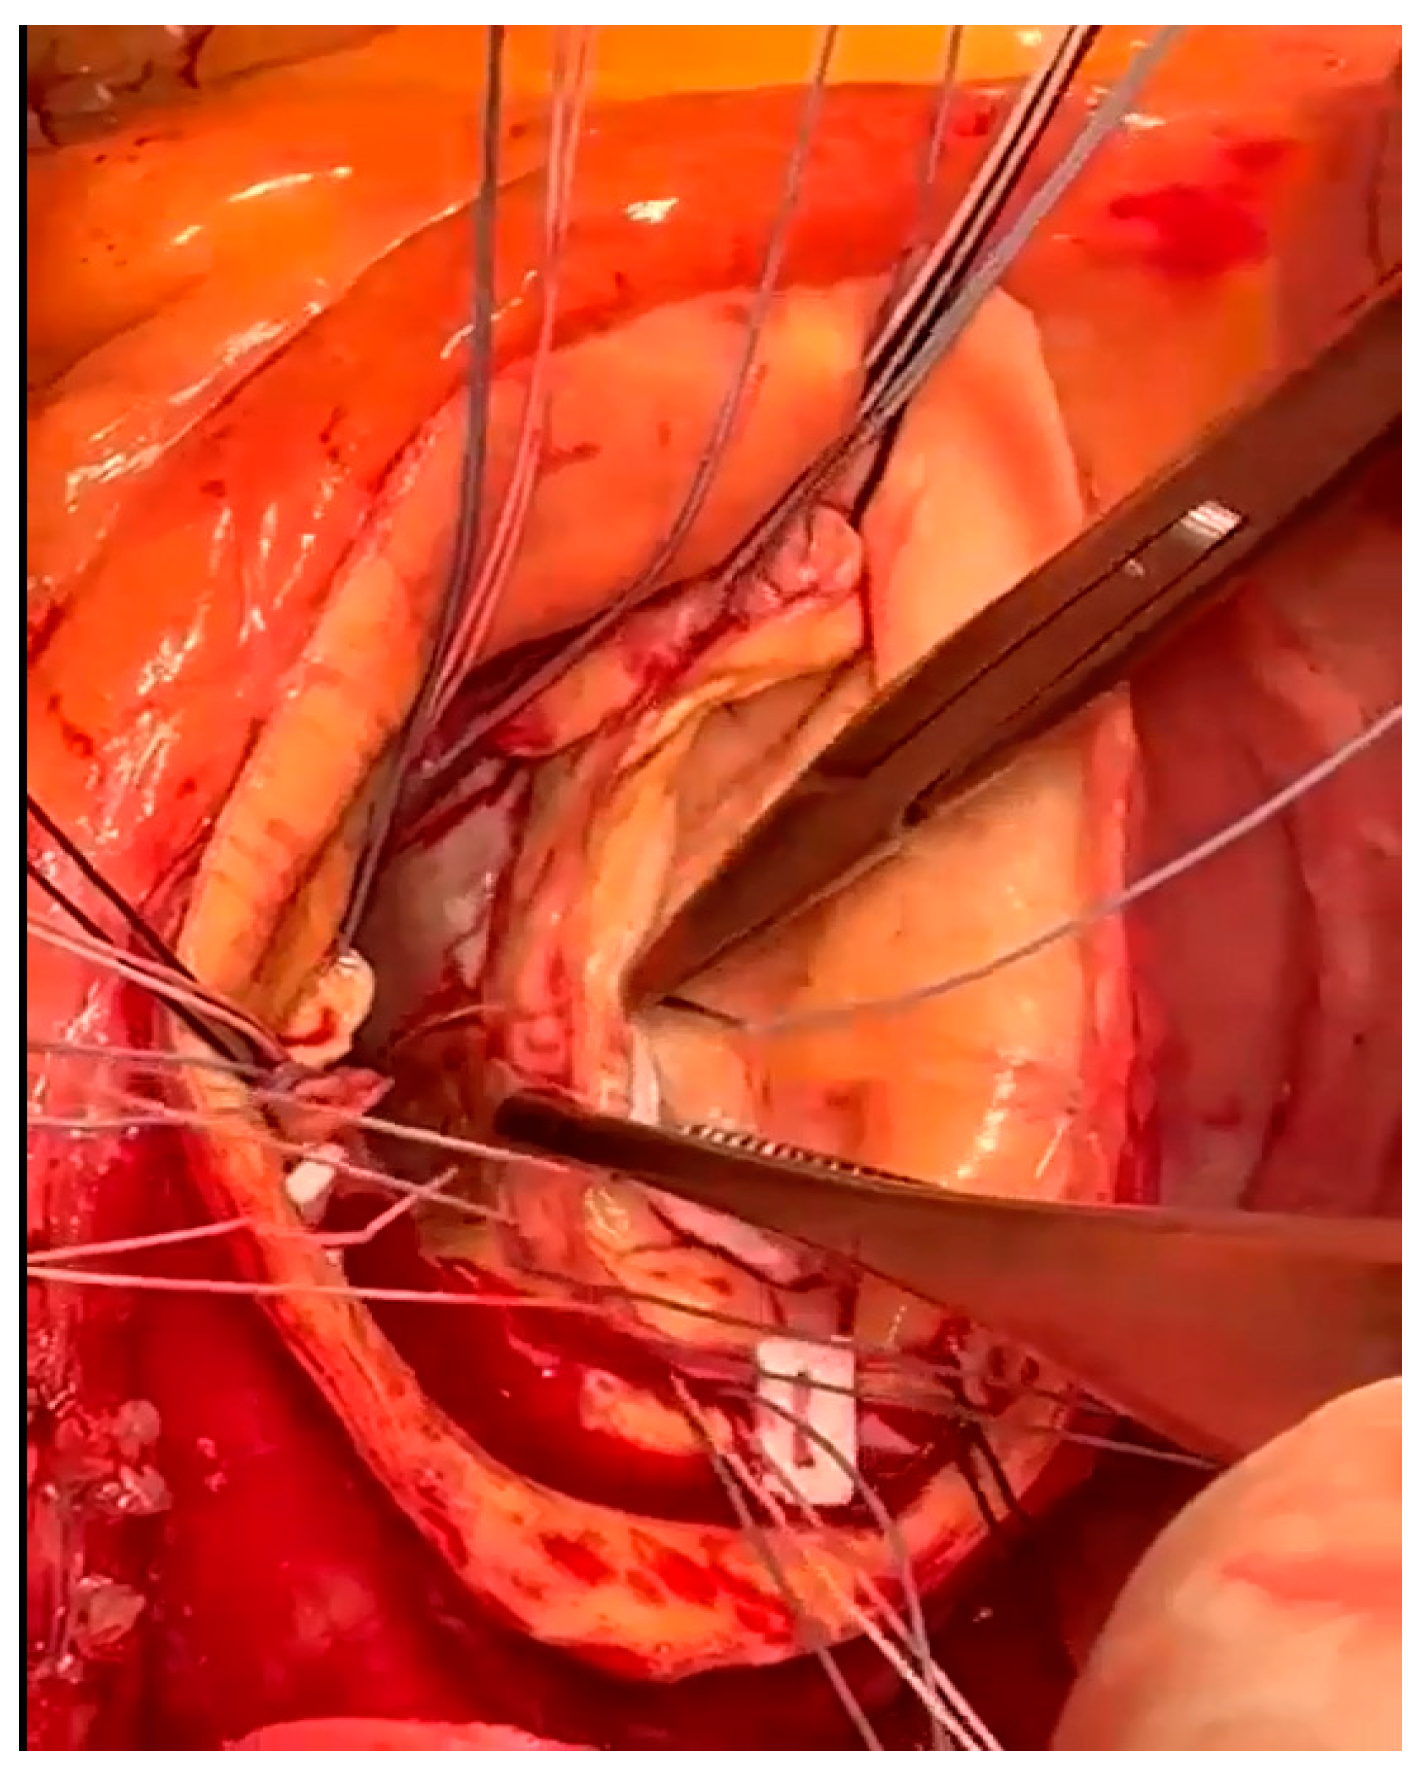

2.4. Surgical Technique